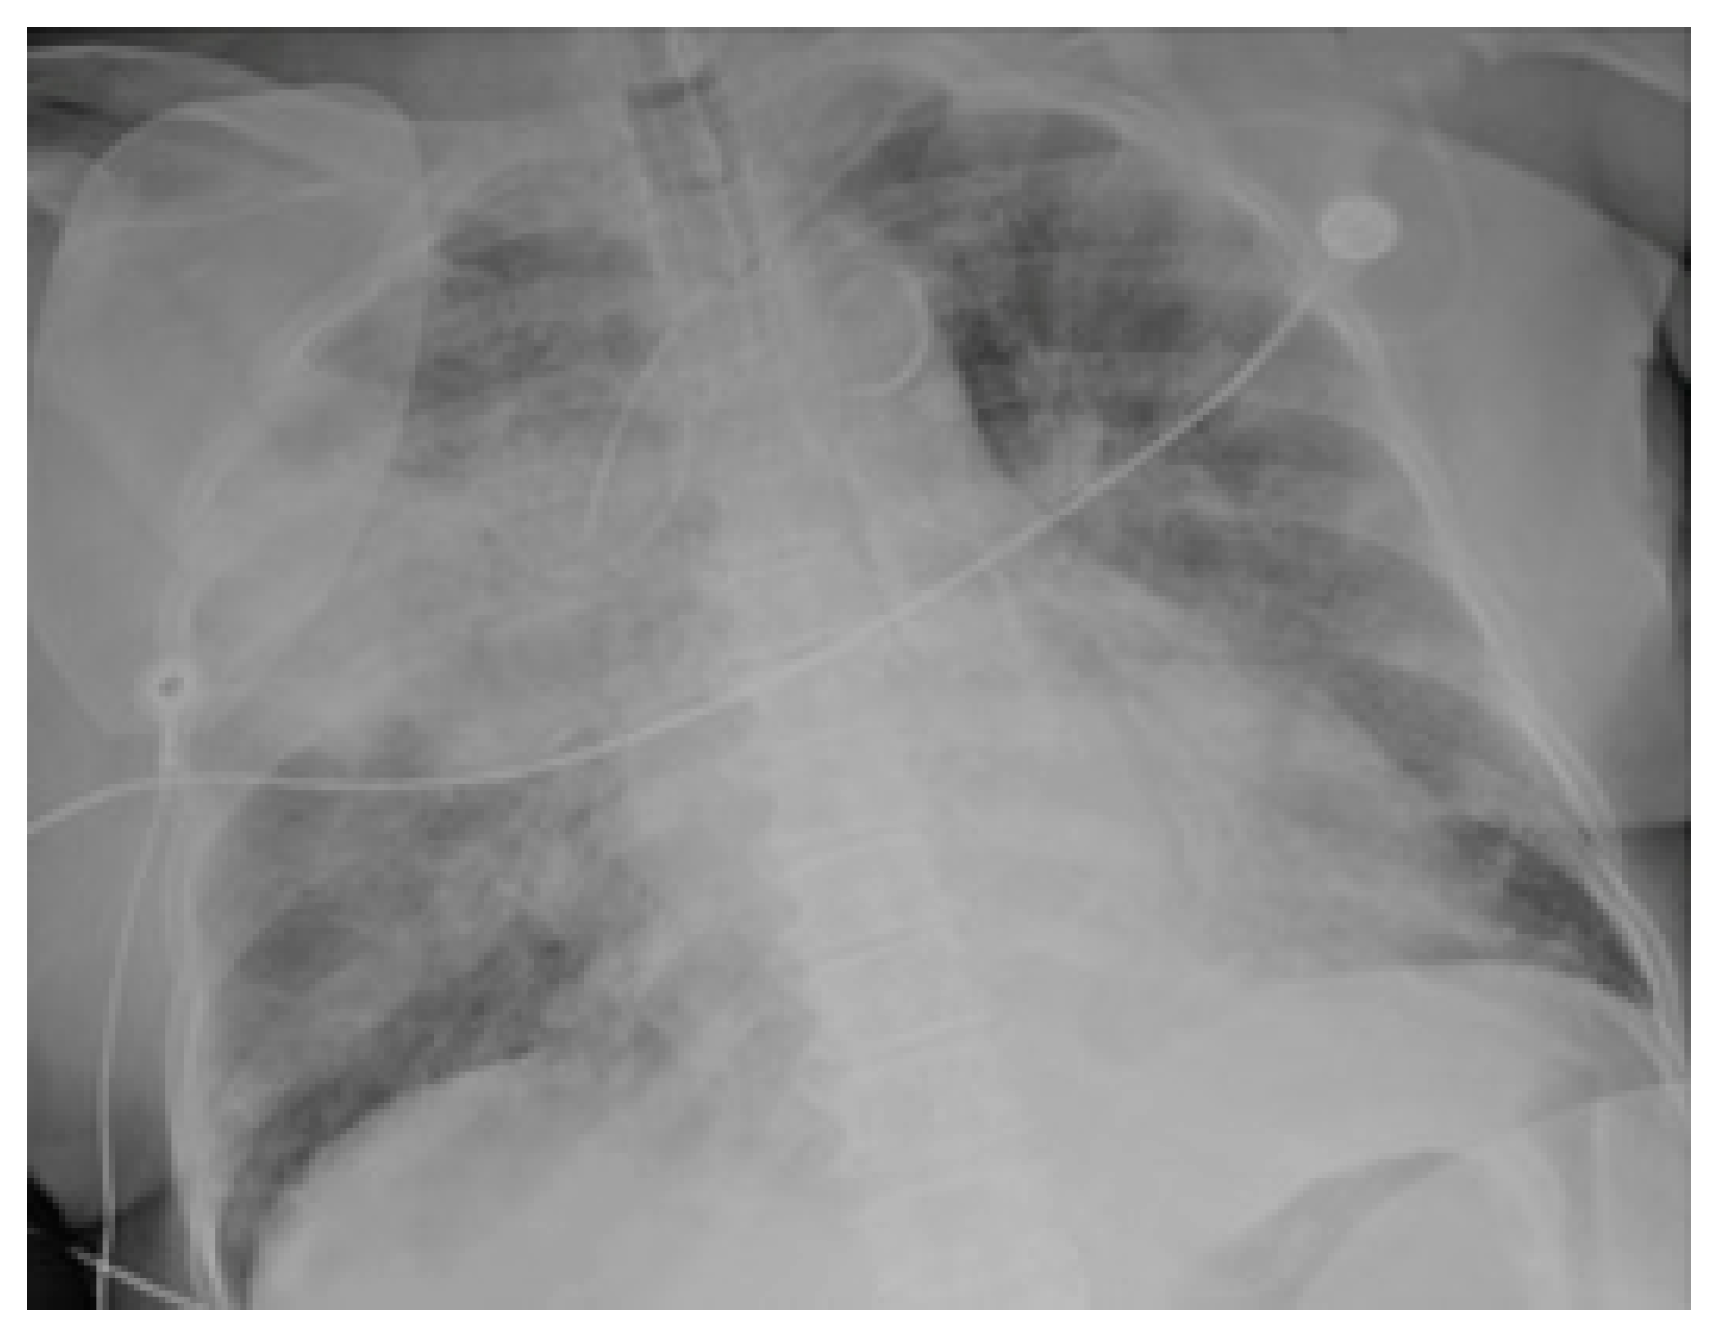

2.3. Imaging and Analysis

3. Results